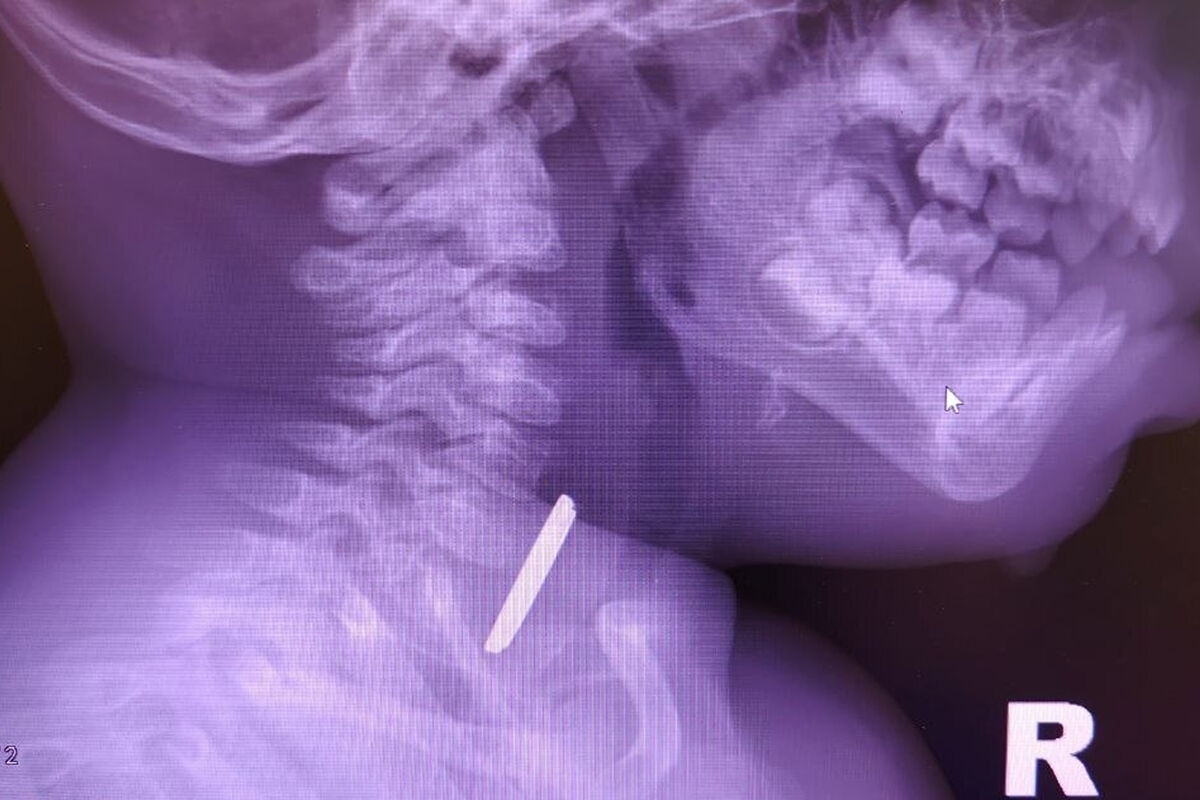

Врачи окружной детской больницы в Нижневартовске спасли годовалого ребенка, который проглотил батарейку. Об этом сообщили в пресс-службе медицинского учреждения.

Маленький пациент поступил в больницу с затрудненным глотанием и слюноотделением. Ребенка направили на рентген, который показал наличие батарейки в верхней трети пищевода. Пациента направили направили на экстренную операцию, и под наркозом извлекли предмет, который уже успел причинить здоровью младенца вред.

«Батарейка повредила стенку пищевода, вызвав глубокий электрохимический ожог, занимающий половину просвета пищевода. Учитывая тяжесть состояния от полученной травмы, ребенок был госпитализирован в отделение реанимации, где проводилась интенсивная терапия», — рассказал детский хирург детской больницы Вячеслав Воронин.